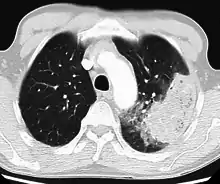

| Chest X-ray of a pneumonia caused by influenza and Haemophilus influenzae, with patchy consolidations, mainly in the right upper lobe (arrow) | |

X-ray presentations of pneumonia may be classified as lobar pneumonia, bronchopneumonia, lobular pneumonia, and interstitial pneumonia.[73] Bacterial, community-acquired pneumonia classically show lung consolidation of one lung segmental lobe, which is known as lobar pneumonia.[41] However, findings may vary, and other patterns are common in other types of pneumonia.[41] Aspiration pneumonia may present with bilateral opacities primarily in the bases of the lungs and on the right side.[41] Radiographs of viral pneumonia may appear normal, appear hyper-inflated, have bilateral patchy areas, or present similar to bacterial pneumonia with lobar consolidation.[41] Radiologic findings may not be present in the early stages of the disease, especially in the presence of dehydration, or may be difficult to interpret in the obese or those with a history of lung disease.[24] Complications such as pleural effusion may also be found on chest radiographs. Laterolateral chest radiographs can increase the diagnostic accuracy of lung consolidation and pleural effusion.[40]

A CT scan can give additional information in indeterminate cases[41] and provide more details in those with an unclear chest radiograph (for example occult pneumonia in chronic obstructive pulmonary disease). They can be used to exclude pulmonary embolism and fungal pneumonia, and detect lung abscesses in those who are not responding to treatments.[40] However, CT scans are more expensive, have a higher dose of radiation, and cannot be done at bedside.[40]